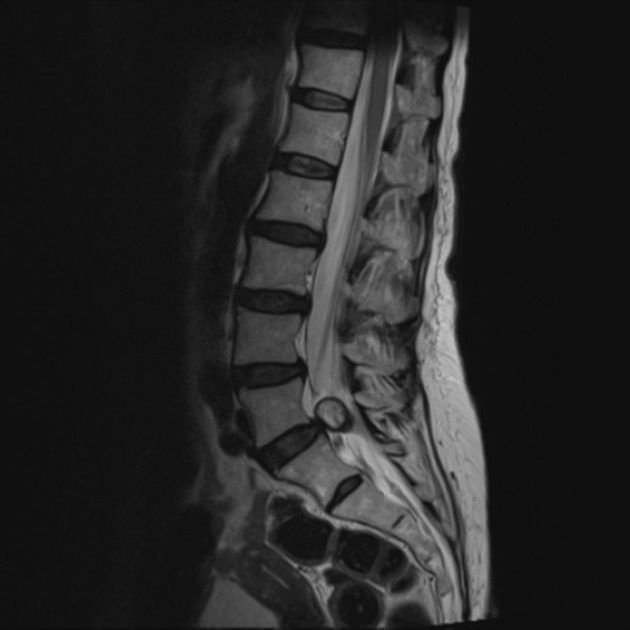

- Rezonans magnetyczny (MRI): Pozwala na precyzyjne zobrazowanie torbieli oraz oceny jej wpływu na struktury nerwowe..

- Torbiel synowialna to łagodna zmiana powstająca w wyniku nagromadzenia płynu w obrębie stawu międzykręgowego. Powstaje z błony maziowej, która w normalnych warunkach wytwarza płyn smarujący stawy. W przypadku zwyrodnienia lub przeciążenia stawów, produkcja tego płynu może się zwiększać, co prowadzi do powstania torbieli.

Torbiel synowialna najczęściej występuje w odcinku lędźwiowym kręgosłupa, ale może także pojawić się w innych jego częściach. Choć sama torbiel jest łagodną zmianą, jej obecność może powodować objawy wynikające z ucisku na struktury nerwowe.